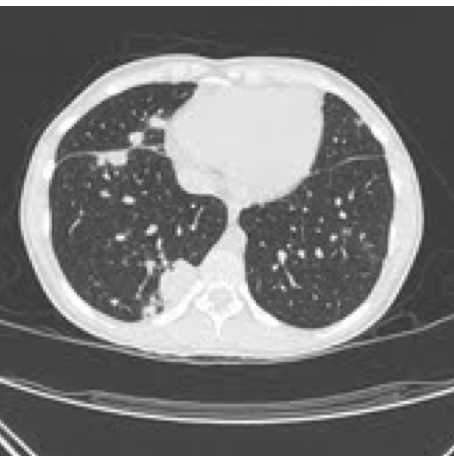

A 25-year-old, previously healthy, active duty marine presents with recurring fevers, night sweats, sore throat, cough productive of yellowish sputum, lethargy, and a dull frontal headache for 7 days. Review of the electronic medical record shows that he has had several previous visits over the last 3 weeks for respiratory symptoms, arthralgia, and loose stools that have been unresponsive to antibiotics, nonsteroidal anti-inflammatories, and metered-dose inhalers. He recently returned from Afghanistan where he was assigned to the public affairs officer and was engaged in community outreach. For his last mission, he visited a village of goat herders and drank milk offered during a meeting with local village elders. The patient appears ill and uncomfortable, complains of dyspnea, and has new right-sided pleuritic chest pain. He is soaked in sweat and is shaking in the bed. His vital signs include a temperature of 38.9°C, heart rate of 124/min, and BP of 85/40 mm Hg. There is cervical adenopathy and decreased breath sounds at the right lung base. Chest CT reveals diffuse lung nodules (Figure 1). He is started on broad-spectrum antibiotics. Labs demonstrate leukopenia, mild anemia, elevation of erythrocyte sedimentation rate and C-reactive protein, and mildly elevated transaminase values. Blood cultures, BAL bacterial cultures, BAL fungal cultures, and BAL acid-fast bacilli smears are negative. The patient remains ill with recurring fevers on a nightly basis, and oxygenation deteriorates progressively. A surgical biopsy specimen from one of the lung nodules is shown (Figure 2). What is the best therapy for his underlying condition?

This case illustrates the uncommon presentation of a common disease entity. Although pulmonary nodules are a rare manifestation of brucellosis (1%-4% of cases), this disease should be suspected in patients with compatible symptoms who have traveled in endemic regions.

The presentation of recurring fevers, night sweats associated with pulmonary abnormalities, noncaseating granulomas on lung biopsy, and recent travel lead to a broad differential that includes TB, sarcoidosis, lymphoma, and fungal disorders. The severe leukopenia and anemia are suggestive of an intracellular pathogen, the three most common of which are Brucella, Salmonella, and Ehrlichia. The negative acid-fast bacilli smears/cultures, negative fungal stains/cultures, and a recent exposure to unpasteurized dairy in a part of the world endemic with brucellosis point to brucellosis as the most likely etiology over sarcoid, TB, or fungal infection. Treatment is often difficult, and relapse can occur (more common with monotherapy). Treatment should include a minimum of two-drug therapy with doxycycline and an aminoglycoside (streptomycin or gentamicin) (choice A is correct; choices B, C, and D are incorrect).